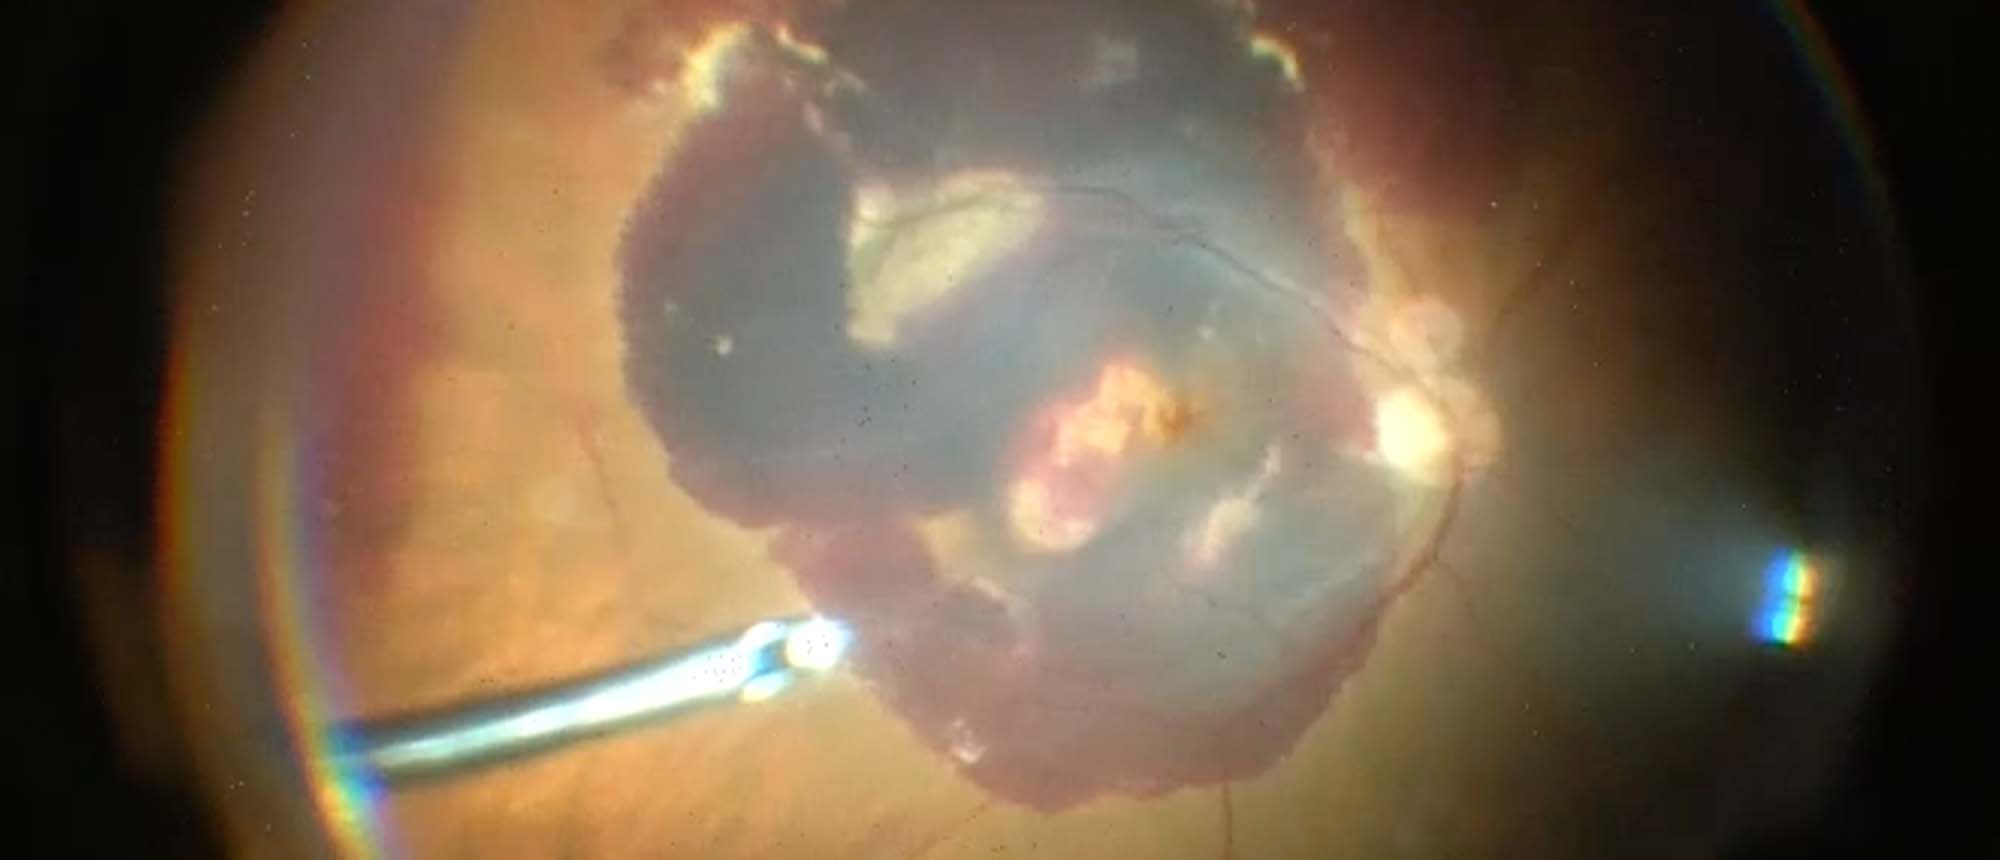

Abstract A patient presented with uncontrolled intraocular pressure (IOP) on maximum medical therapy and had bilateral laser iridotomy. The patient was diagnosed with angle-closure glaucoma. Biometry measurements were consistent with nanophthalmos. The right eye underwent phacoemulsification with a…

Nanophthalmos with Angle Closure Glaucoma A patient presented with uncontrolled intraocular pressure (IOP) on maximum medical therapy and had bilateral laser iridotomy. The patient was diagnosed with angle-closure glaucoma. Biometry measurements were consistent with nanophthalmos. The right eye und…